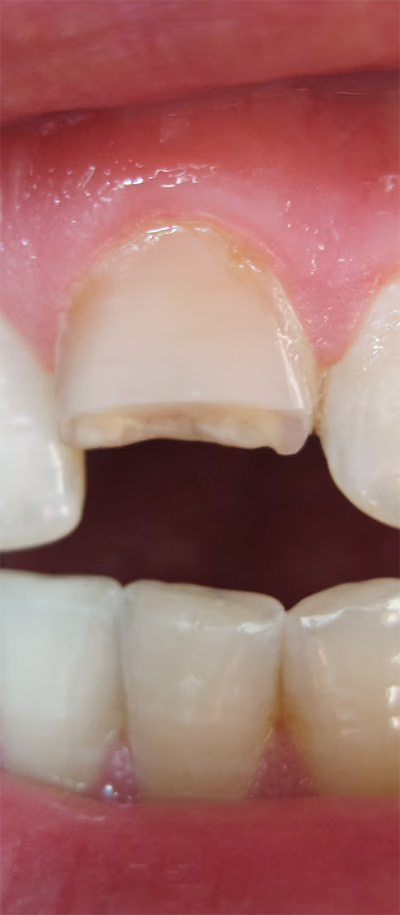

Broken or infected teeth can result from trauma, decay, or poor oral hygiene. Our team evaluates each tooth carefully to determine if it can be saved with restorative treatments, including fillings, crowns, or root canal therapy. When preservation is not possible, we perform tooth extraction with gentle techniques and anesthesia for comfort. Post-extraction, dental implants are recommended to restore chewing function, aesthetics, and long-term oral health.